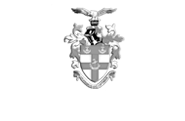

A 44 year old right handed male presented for a routine eye examination.

On questioning, he had been experiencing increasing headaches for the past 2 months. He had two headaches in total which presented as follows;

- blurred vision followed by headache

- can’t see anything on right hand side, aura for 30 mins, headaches lasted ½ day, always on right side

- persistent visual field loss post migraine

- some short-term memory loss

The patient has L occipital arteriovenous malformation (AVM). Stereotactic radiosurgery was performed with good results. The patient still experiences migraine headaches but without aura. He also has a persistent visual field defect due to scarring from AVM.